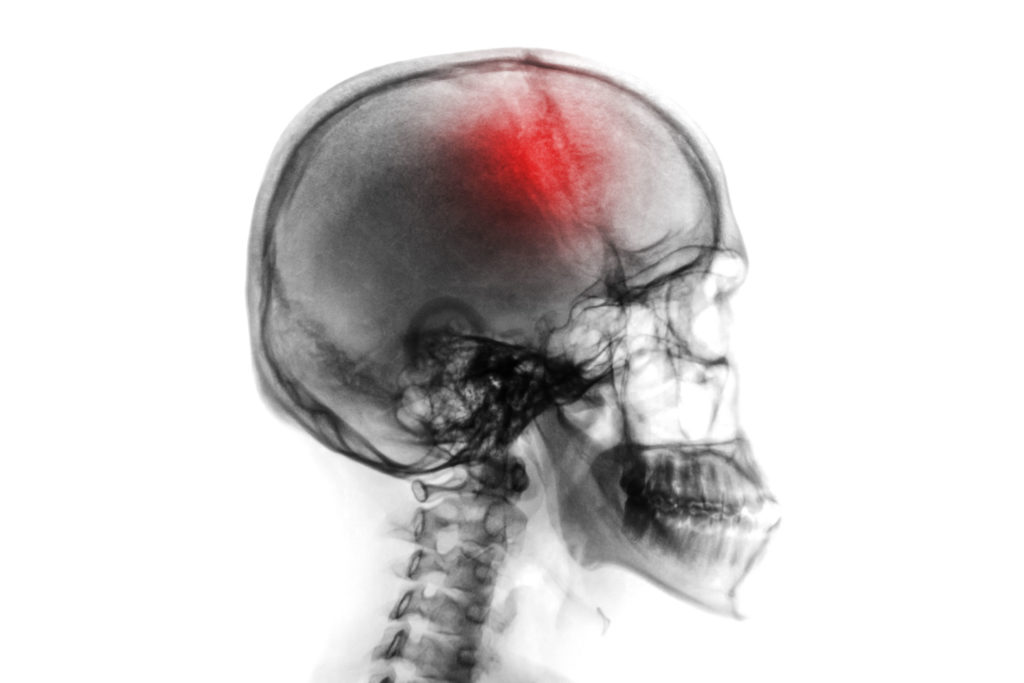

A traumatic brain injury can change your life in an instant. Many events can lead to brain injuries in Las Vegas, including car wrecks, assault, slip and fall accidents, medical errors, etc. Although some brain injuries, like a mild concussion, resolve quickly and leave no lingering symptoms, other blows to the head may result in chronic health issues and lengthy rehabilitation times, not to mention exorbitant medical bills.

A traumatic brain injury and its long term effects can vary greatly in severity. While some may make full recoveries in a matter of weeks or months, others who experience a head injury may struggle with basic tasks for years or even the rest of their life. Some may even be left in a vegetative state until they ultimately succumb to their injuries.